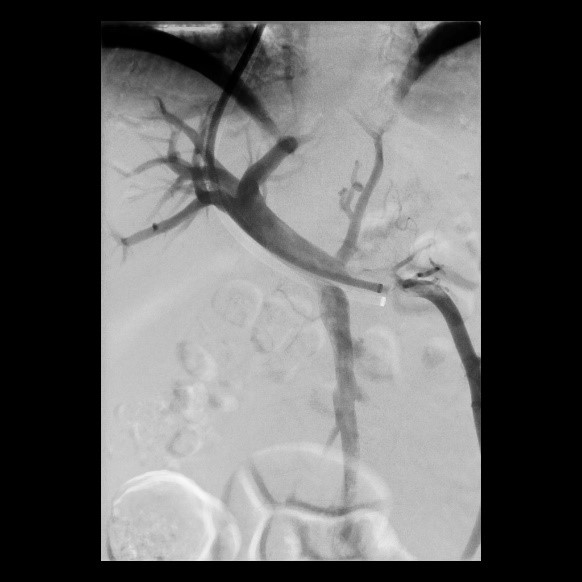

Erfolgreiche Implantation eines transjugulären intrahepatischen portosystemischen Shunts (TIPSS) bei Leberzirrhose und refraktärem Aszites. Darstellung der Lebervenen

(Bild 2 von 4)

Erfolgreiche Implantation eines transjugulären intrahepatischen portosystemischen Shunts (TIPSS) bei Leberzirrhose und refraktärem Aszites. Transhepatische Punktion der Pfortader unter sonographischer Kontrolle

(Bild 3 von 4)

Erfolgreiche Implantation eines transjugulären intrahepatischen portosystemischen Shunts (TIPSS) bei Leberzirrhose und refraktärem Aszites. Implantation eines Stentgrafts

(Bild 4 von 4)